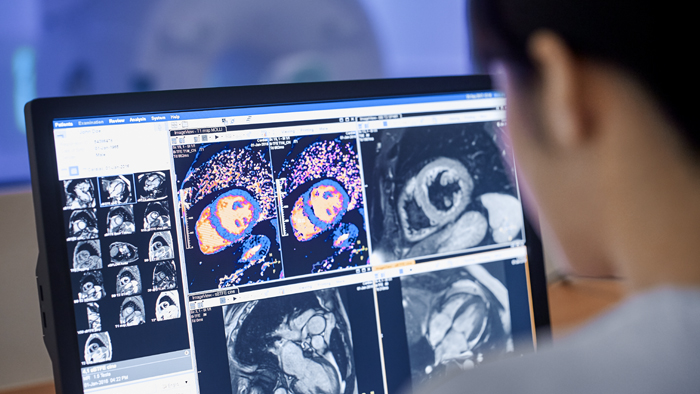

June 2023 – Philips Fieldstrength MRI Customer Story

Impact of Compressed SENSE on cardiac MR services at Nottingham University Hospitals.

Philips’ Compressed SENSE is a breakthrough acceleration technique that shortens single MRI sequences and full MRI examinations. It can be applied in all anatomies and all contrasts, in 2D, 3D, dynamics and 4D MRI. It might be presumed that Compressed SENSE allows shortening of all cardiac magnetic resonance (CMR) scan times and it certainly does for cines, flow measurement, late gadolinium enhancement (LGE) and multishot black blood by allowing shorter breath holds.

But some cardiac MR scans are fixed in length, such as single shot black blood and T1 mapping which limit acquisition to one image per beat. Even if each source image is acquired faster, the scan still takes the same number of heart beats. Similarly, for perfusion, the scan duration is matched to the duration of the first-pass of contrast agent through the heart; higher acceleration factors do not result in a shorter scan time. Compressed SENSE does not shorten the scan time of these scans, but it still has a significant impact by enabling shorter data readouts; the data is less affected by the motion of the heart beating. This produces crisper CMR images and can increase diagnostic confidence for the expert reader

Better patient experience leads to improved diagnostic confidence

At Nottingham City Hospital, Kevin Strachan is the cardiac lead radiographer and manages the day-to-day of a busy clinical MRI service, as well as reporting a range of examinations and referrals. He has used Compressed SENSE extensively, and remarks on the impact it has for viability studies. This is because for many patients, LGE is the most important scan, and often it is the last scan to be acquired - when patients can be fatigued from previous breath holding. Using Compressed SENSE, the duration and number of breath holds prior to the LGE scan can both be reduced. Mr. Strachan reported, “This is a big impact to our clinical service – the patient is less tired for the LGE scan and can perform a better breath hold. Whilst our LGE scans were normally diagnostic without Compressed SENSE, speaking to our imaging Consultant Cardiologists, we now have a better quality of LGE imaging in circumstances where we would have normally struggled - such as poor breath-holders and arrhythmic patients.”